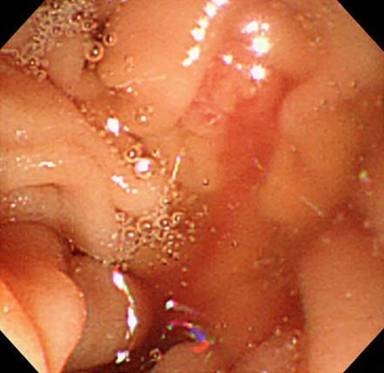

An emergency intervention was then carried out. Angiography clearly revealed a fusiform aneurysm of the middle-distal splenic artery and narrowing of the proximal splenic artery (Figure 4a). All parts of the splenic artery were successfully coil-embolized (Figure 4b). Twenty days later, intervention for dissection of the celiac artery was performed. The celiac artery including the false lumen was successfully coil-embolized (Figure 4c). The patient has since shown no recurrence of the epigastric pain or melena.

Figure 4. a. Angiography of the celiac artery clearly showing the narrowing of the proximal splenic artery (small arrow) and a fusiform aneurysm of the middle-distal splenic artery (large arrow). b. Angiography of the celiac artery showing that all parts of the splenic artery were successfully coil-embolized. c. Lateral angiography of the celiac artery showing that the celiac artery including the false lumen was successfully coil-embolized. |